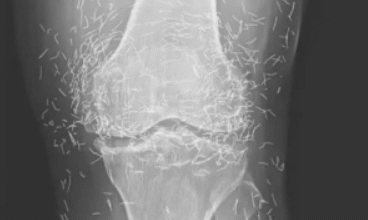

Zdjęcie rentgenowskie ujawniło setki złotych igieł w kolanach kobiety

Lekarze badając zdjęcie rentgenowskie kolan starszej kobiety cierpiącej na silny ból stawów, odkryli prawdziwą żyłę złota: setki maleńkich złotych igieł do akupunktury pozostawionych